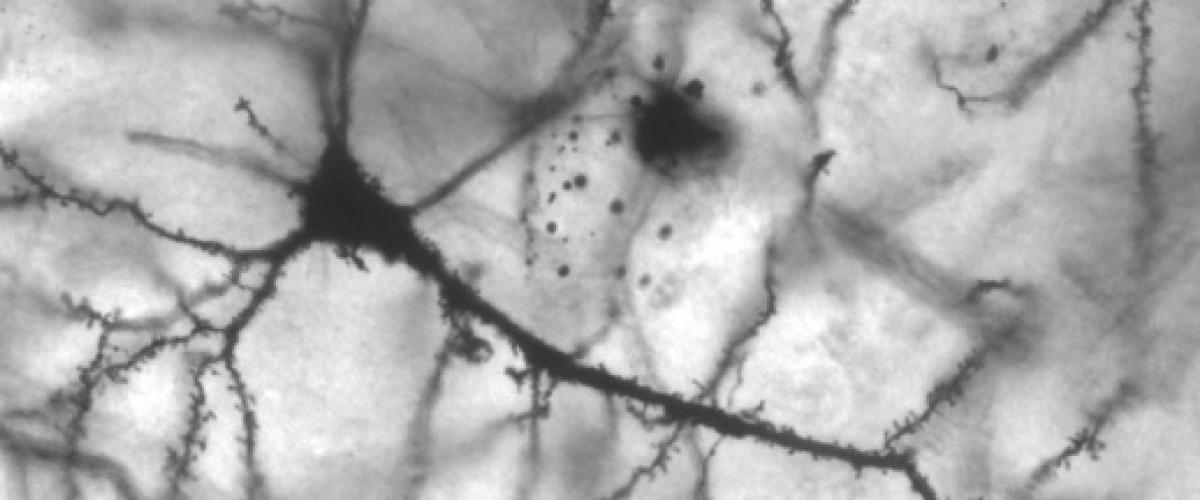

Parkinson's Disease: The Stars in Our Brains

More than 10 million people worldwide—about 1 percent of people over age 60—live with Parkinson’s disease. There are treatments that can help control symptoms, but there is no cure.